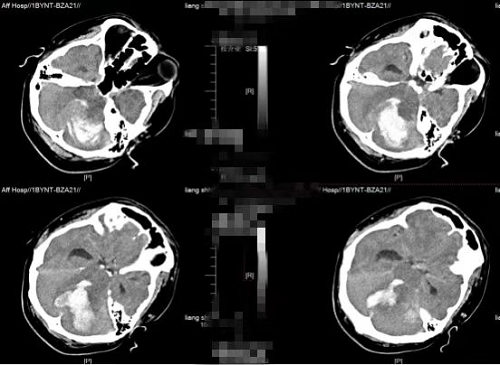

急诊科当即为患者开辟绿色通道,以全力赴抢救患者为先,及时为桂先生进行心肺复苏、气管插管、呼吸机辅助呼吸。神经外科二区伍贞宇医生在接到急诊科通知后,第一时间赶到急诊科评估病情,同时汇报神经外科二区科主任王鹏主任。该患者当时已处于深度昏迷状态,双侧瞳孔直径约2mm,对光反应消失,无自主呼吸及心跳。在协同急诊科抢救后患者心跳恢复,但仍无自主呼吸,病情仍十分危重,急诊行CT提示“左侧小脑半球脑出血并破入脑室,第四脑室及脑干受压,继发幕上脑室轻度脑积水,环池消失。”,脑内出血较前明显增多,脑疝形成,需立即进行手术。

图1术前CT